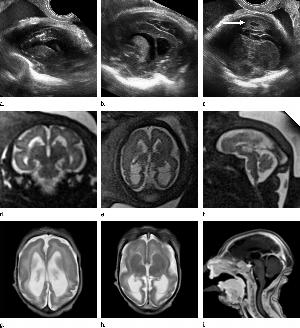

Figure 5. Images obtained in the case of a 33-year-old woman who had a rash at 10 weeks of pregnancy, with confirmed Zika virus infection. US performed at 19 weeks of gestational age showed a head circumference in the normal range (16.6 cm). (a, b) Sagittal and (c) coronal transvaginal US images obtained at the next US examination at 27 weeks 2 days of gestational age, however, showed the fetal head circumference to be 21.6 cm, which corresponded to 23 weeks 3 days (˂2.3 percentile, not shown). There was mild ven¬triculomegaly with septations in the occipital horns. Calcifications could be seen at the gray matter–white matter junction. The cerebrum was atrophic. There was blood clot in the region of the confluence of sinuses (arrow on c). (d) Coronal, (e) axial, and (f) sagittal T2- weighted fetal MR images obtained at 32 weeks show septations in the ventricles and an abnormal-appearing cortex, with a thickened and undersulcated cortex most marked on the left, compatible with polymicrogyria. The sagittal midline view shows microcephaly, blood clot in the region of the confluence of sinuses, and prominent skin folds. (g, h) Axial T2-weighted and (i) sagittal T1-weighted postnatal MR images obtained in the 4-week-old neonate show diffuse gyral abnormality and abnormal myelination. The septations in the ventri¬cles are again seen. The sagittal image shows thinning of the spinal cord at the craniocervical junction.

High-res (TIF) version

Figure 6. Images obtained in the case of a 24-year-old woman pregnant with twins, with characteristic rash at 9 weeks of pregnancy and confirmed Zika virus infection. (For each pair of images, the first image is of twin A, and the second image is of twin B.) At 14 weeks of gestational age, the fetal head size of both twins was normal. The head size never went below the 3rd percentile for either fetus in examinations at 19–28 weeks. (a, b) Sagittal and (c, d) axial fetal MR images were obtained at 36 weeks. (e, f) Axial and (g, h) surface reconstruction postnatal CT images and (i, j) axial T2-weighted and (k, l) coronal MR images were obtained 1 week after delivery at 38 weeks of gestational age. There is severe microcephaly with profound frontal lobe hypoplasia. Calcifications in the subcortical white matter at the gray matter–white matter junction are visualized. Both twins have a flattened appearance of the pons. The spinal cord is atrophic (best seen on a). Redundant skin is seen in the occipital region. There is polymicrogyria involving the frontal and parietal regions and atrophic cortex and white matter in the occipital regions. Each twin has hypoplasia of the corpus callosum, with prominent fornices. There is abnormal myelination in the occipital region that, in twin A (i), has the appearance of a cyst or septation within the ventricle. The cerebellum is somewhat small and nodular. There is lack of rotation of the hippocampi.